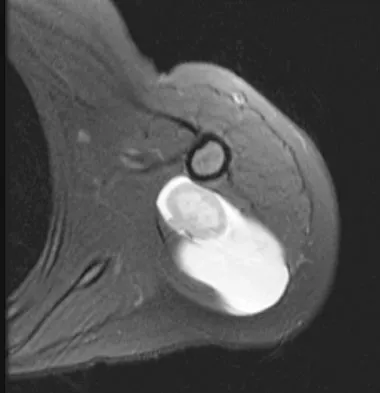

Figure 47 shows a transverse MRI scan of a patient's left shoulder. The findings reveal which of the following abnormalities?

The MRI scan shows a defect in the posterior aspect of the humeral head, commonly referred to as a Hill-Sachs lesion. This is an impaction fracture of the humeral head that occurs during anterior shoulder dislocation. The abnormality on this image is an irregularity of the posterior humeral head; the humeral head otherwise has a homogenous appearance. The coracoid, subscapularis, and posterior labrum are normal. Griffin LY (ed): Orthopaedic Knowledge Update: Sports Medicine. Rosemont, IL, American Academy of Orthopaedic Surgeons, 1994, pp 47-63.